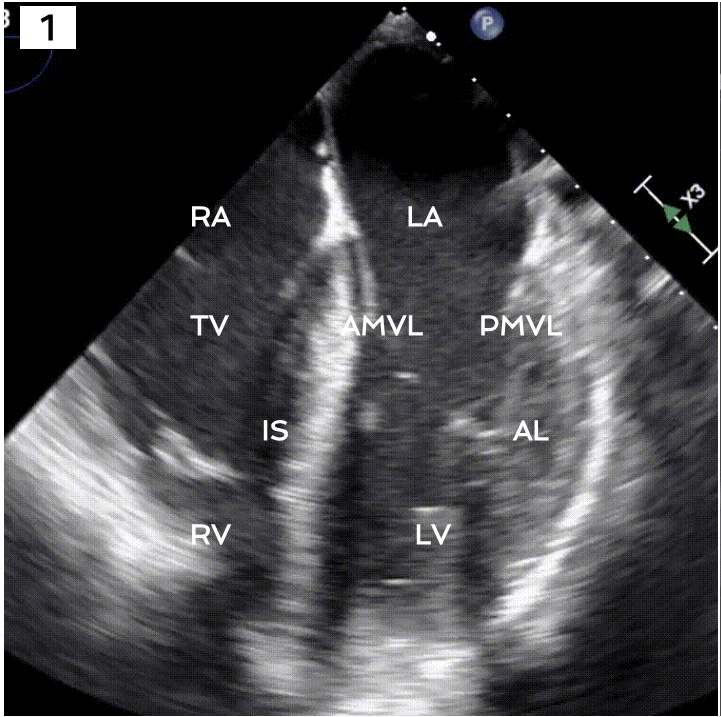

Identify the view and structures

Apical 4 chamber